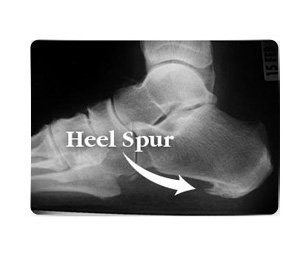

Art. talocruralis og foden